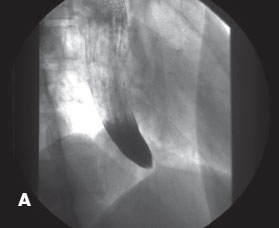

Achalasia

Christopher Knudsen, DO; Terry J. Hundley, MD; Gregory W. Rutecki, MD

<div id="article-content-body"><p><img src="/sites/default/files/images/Achalasia_April_2011_figA%26B.jpg" style="float: left; margin-left: 8px; margin-right: 8px;...